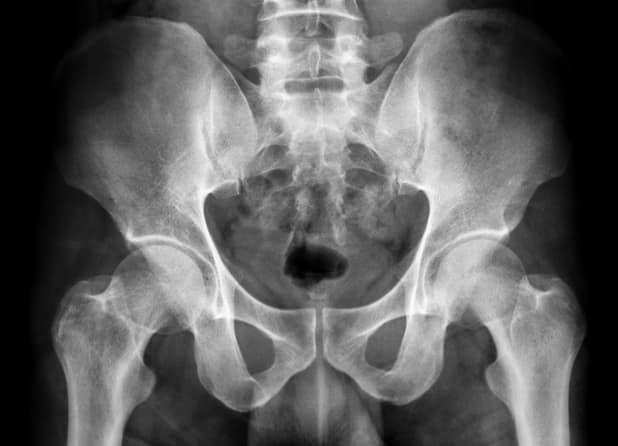

The hip is a simple ball-and-socket joint where the thigh bone joins with the pelvis. The hip is the largest weight-bearing joint1 in the human body and is supported by muscles, cartilage, and ligaments. These structures surrounding the hip help to cushion the joint and allow it to work smoothly without pain.

A hip may become diseased with arthritis or injured during a fall, which may reduce mobility and may cause pain during movement or even at rest. When arthritis wears away the cartilage, the hip bones may start rubbing together, which can be painful and may cause damage to the surface of the bones.The damaged bone and cartilage may cause joint pain and limit range of motion.

How Does Your Hip Work?

When the hip becomes diseased or injured, its natural balance and function may be disrupted, which potentially causes pain, limits mobility, or creates other medical challenges.

Pelvis

Femoral Head

Femur